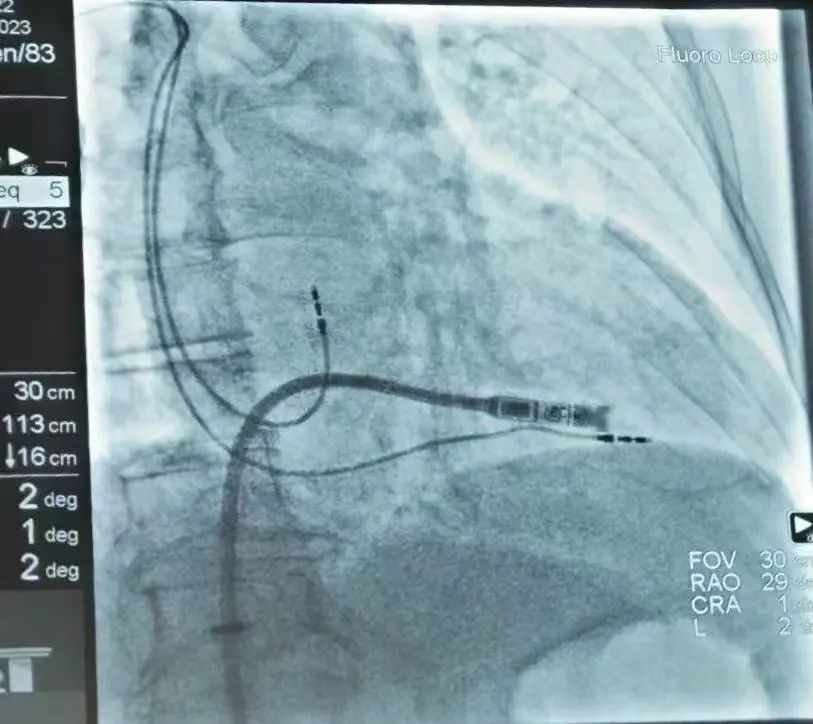

无导线起搏器植入过程

在哈医大二院李述峰老师的指导下,手术在局部麻醉下进行,通过股静脉穿刺,将起搏器通过导管植入到心腔内部,手术时间仅有30分钟,患者术后反应良好,两天后即可恢复正常的工作和生活。